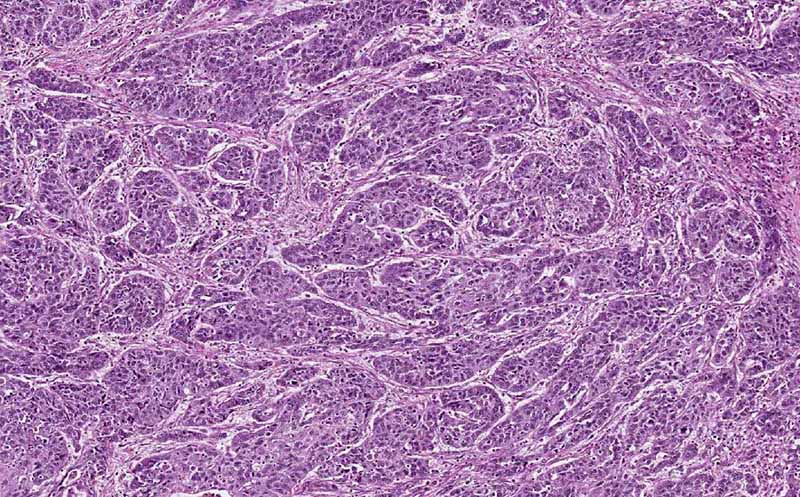

Hematoxylin & eosin

Area 1: The cells here for irregular cell nests. Based on the morphology, this can be a neuroendocrine carcinoma. However, the possibility of an adenocarcinoma cannot be entirely ruled out. Immunohistochemistry and examination of other part of the tumor can be helpful but both cannot be performed with this archival specimen.

• This image is taken from the wall of a segment of colon. You can recognize the muscle layer. There are two disease processes. The first process is composed of nests of pleomorphic cells (Area 1). The pathologic features are that of a neoplasm of the colon. This is most likely the reason why this segment of colon was surgically removed. The pathology are suggestive of a carcinoid but no further information is provided in the archive.